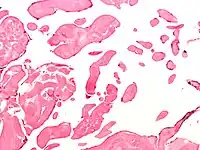

| Low magnification micrograph of an excised aortic valve papillary fibroelastoma showing the characteristic avascular branching papillae, H&E stain | |

Papillary fibroelastoma are typically found and accurately diagnosed by imaging. The diagnosis is confirmed by pathology. Histologically, papillary fibroelastomas have branching avascular papillae, composed of collagen, that are covered by endothelium.